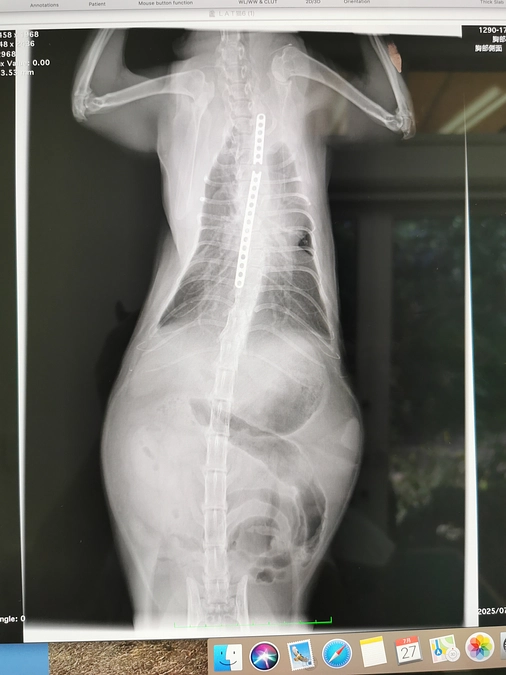

リンパ腫

いつもらいむを応援して下さり、ありがとうございます。本日CT撮影し、折れていたバ-は問題なしでした。しかし、目に腫瘍ができ、精査したら、リンパ腫で全身転移してました。抗がん剤しなければ、数週間の命、効果があれぱ、後何年か生きられるし、全身の苦痛も緩和される。らいむは強い子です。あと少しらいむと共に頑張りたいと思います。皆様見守っていて下さい